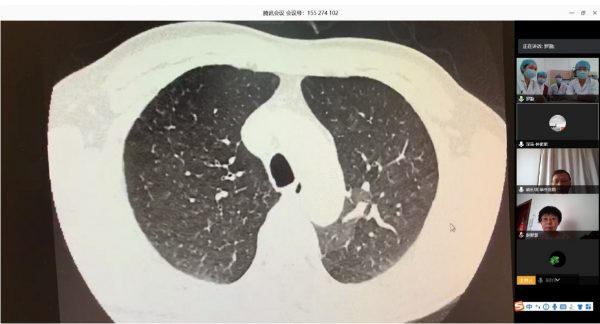

根據(jù)衛(wèi)健委新冠肺炎疫情防控工作總體部署以及醫(yī)院要求, 3月16日,北阜肺血管與血栓一病區(qū)和深阜肺血管病房已同步開始有序收治患者,開展包括右心導(dǎo)管、肺動脈造影及慢性血栓栓塞性肺動脈高壓患者的肺動脈球囊擴張術(shù)等手術(shù)在內(nèi)的肺血管病所有診治。為減少新冠肺炎疫情傳播風(fēng)險,保證深圳肺動脈高壓患者得到最佳診療方案,北阜和深阜兩地肺血管病房充分利用“互聯(lián)網(wǎng)+醫(yī)療”的優(yōu)勢作用,開展遠程線上查房,對每位患者資料進行詳細分析,確定診治方案,使深圳的患者在疫情特殊時期可得到與平時同樣的醫(yī)療服務(wù)。